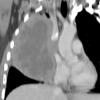

Lymphoma CT Sag

Date: 04/25/2009

Views: 2936